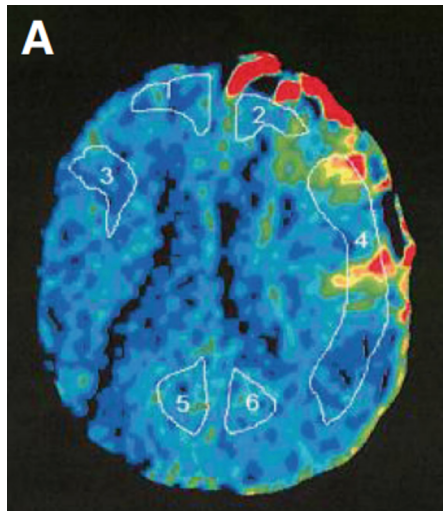

术前血管造影(双侧颈总动脉正位图)显示双侧颈内动脉末端有“烟雾血管狭窄征象”,双侧大脑中动脉(MCA)狭窄(左)。术前Xe-CT显示双侧MCA区域脑血流减少(右:15.9.左:22.8 ml/100 g/min)(右)。